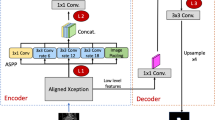

This retrospective study involved analysis of MR images from 169 patients with cervical cancer stage IB–IVA captured; among them, diffusion-weighted (DW) images from 144 patients were used for training, and another 25 patients were recruited for testing. A U-Net convolutional network was developed to perform automated tumor segmentation. The manually delineated tumor region was used as the ground truth for comparison. Segmentation performance was assessed for various combinations of input sources for training. ADC radiomics were extracted and assessed using Pearson correlation. The reproducibility of the training was also assessed.